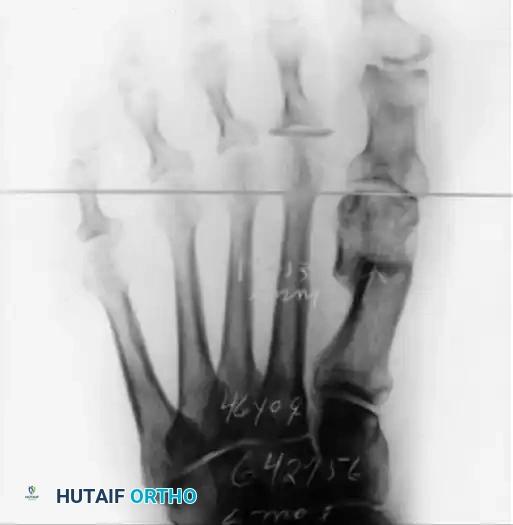

FIGURE 81-28 A: Anteroposterior weight-bearing radiograph demonstrating a failed Mitchell procedure. Note the excessive shortening of the first metatarsal, which has completely disrupted the metatarsal parabola, leading to severe transfer metatarsalgia beneath the second metatarsal head.